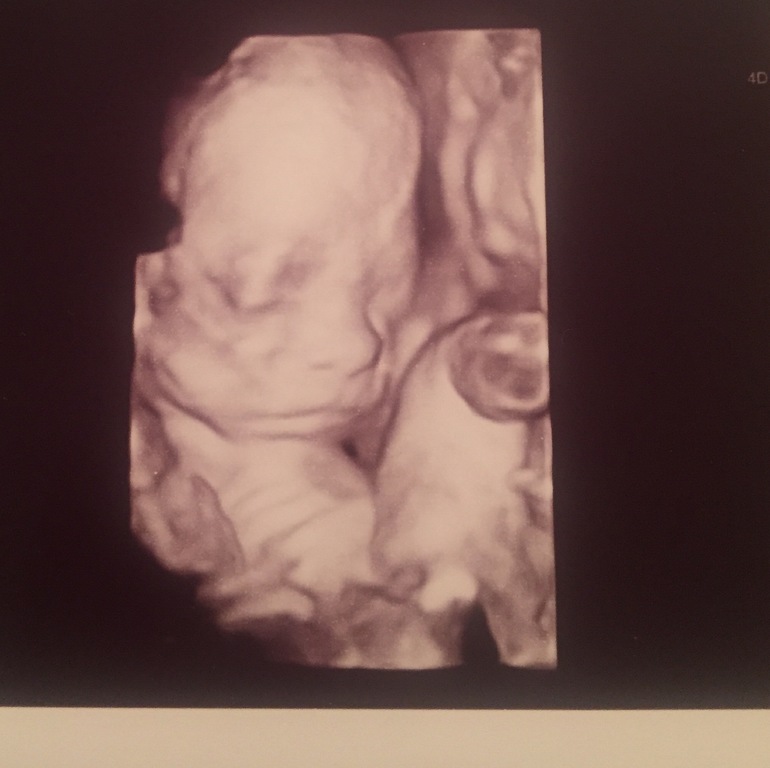

Весила девчонка-320 гр в 20 нед. посмотрели в 3д там такой человечек плавун ножки руками обхватывает умильно!

У нее мой нос! Вот это техника сейчас!